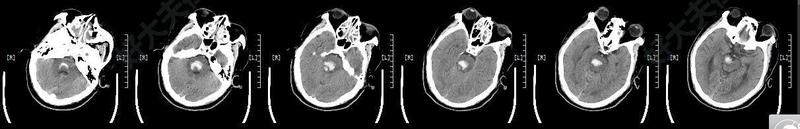

治療前患者中年男性,突發(fā)意識(shí)障礙1小時(shí)入院,頭顱CT片提示:腦干出血,復(fù)查出血較前增多,量大于5ML,患者出現(xiàn)呼吸衰竭,行氣管插管呼吸機(jī)輔助呼吸。治療中急診在神經(jīng)導(dǎo)航下行顱內(nèi)血腫立體定向穿刺引流術(shù),手術(shù)微創(chuàng),定位精準(zhǔn)。治療后治療后12天患者自主呼吸,基本遵囑,復(fù)查頭顱CT大部分血引流干凈,轉(zhuǎn)出重癥監(jiān)護(hù)室